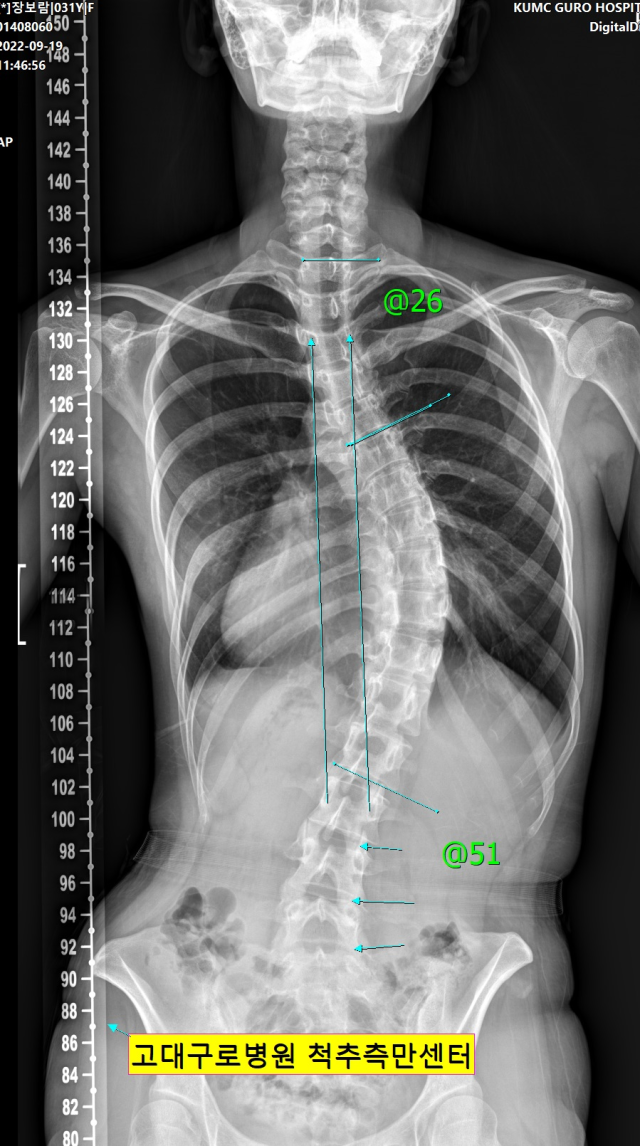

장 씨는 현재 만곡도가 50도 넘는 고도 척추측만증을 갖고 있다. 이는 지체장애인 판정을 받을 수 있을 정도로 심각한 장애다. 남성의 경우 병역판정검사에서 5급 판정을 받아 현역에서 제외될 수 있다. 장 씨는 유년 시절 특발성 척추측만증(원인을 알 수 없이 발생한 척추측만증) 진단을 받은 뒤 정기검진과 교정기, 운동을 장기간 병행했음에도 증세 악화를 막을 수 없었다.